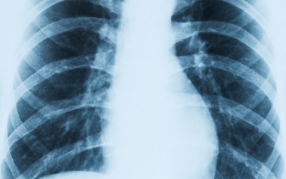

胸痛|肺炎的预防措施 肺炎的主要症状

文章图片

肺炎的预防措施

肺炎的主要症状